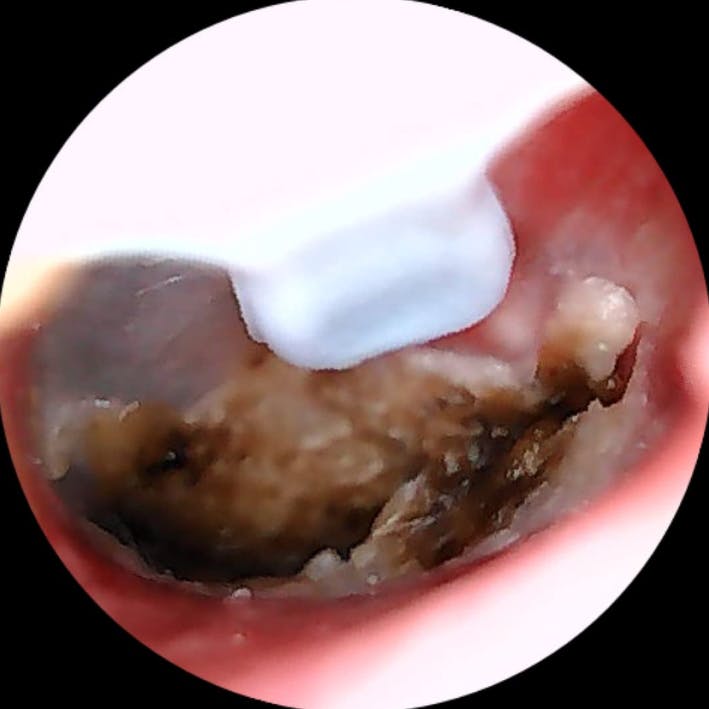

Ich bin wirklich überraschend begeistert von diesem Ohrenendoskop. Die Handhabung ist kinderleicht, die Verbindung zum Smartphone hat auf Anhieb funktioniert und die Bildqualität ist überraschend gut – gestochen scharf und detailreich. So konnte ich mir das Ohrinneres problemlos anschauen und erkennen, was los ist.

Besonders praktisch finde ich das schlanke Design und die integrierte Beleuchtung – dadurch sieht man selbst kleine Details sehr klar. Auch die mitgelieferten Aufsätze und Werkzeuge sind gut verarbeitet und machen die Anwendung noch einfacher und hygienischer.

Ich habe eine starke Ohrenschmalzproduktion und es entstehen regelmäßig Propfen, die in der Vergangenheit regelmäßig vom Ohrenarzt entfernt werden mussten.

Mit diesel Gerät kann ich selbst in regelmäßigen Abständen das Ohr vom gröbsten Ohrenschmalz befreien. Mit diesem Gerät tut es überhaupt nicht weh, die Aufnahmen der Kamera sind sehr gut. Mit etwas Geduld, Übung und Vorsicht kann man das Ohr wirklich sehr gut reinigen, ohne es zu verletzen. Ich kann das Produkt ohne Vorbehalte weiterempfehlen und würde es wieder kaufen.